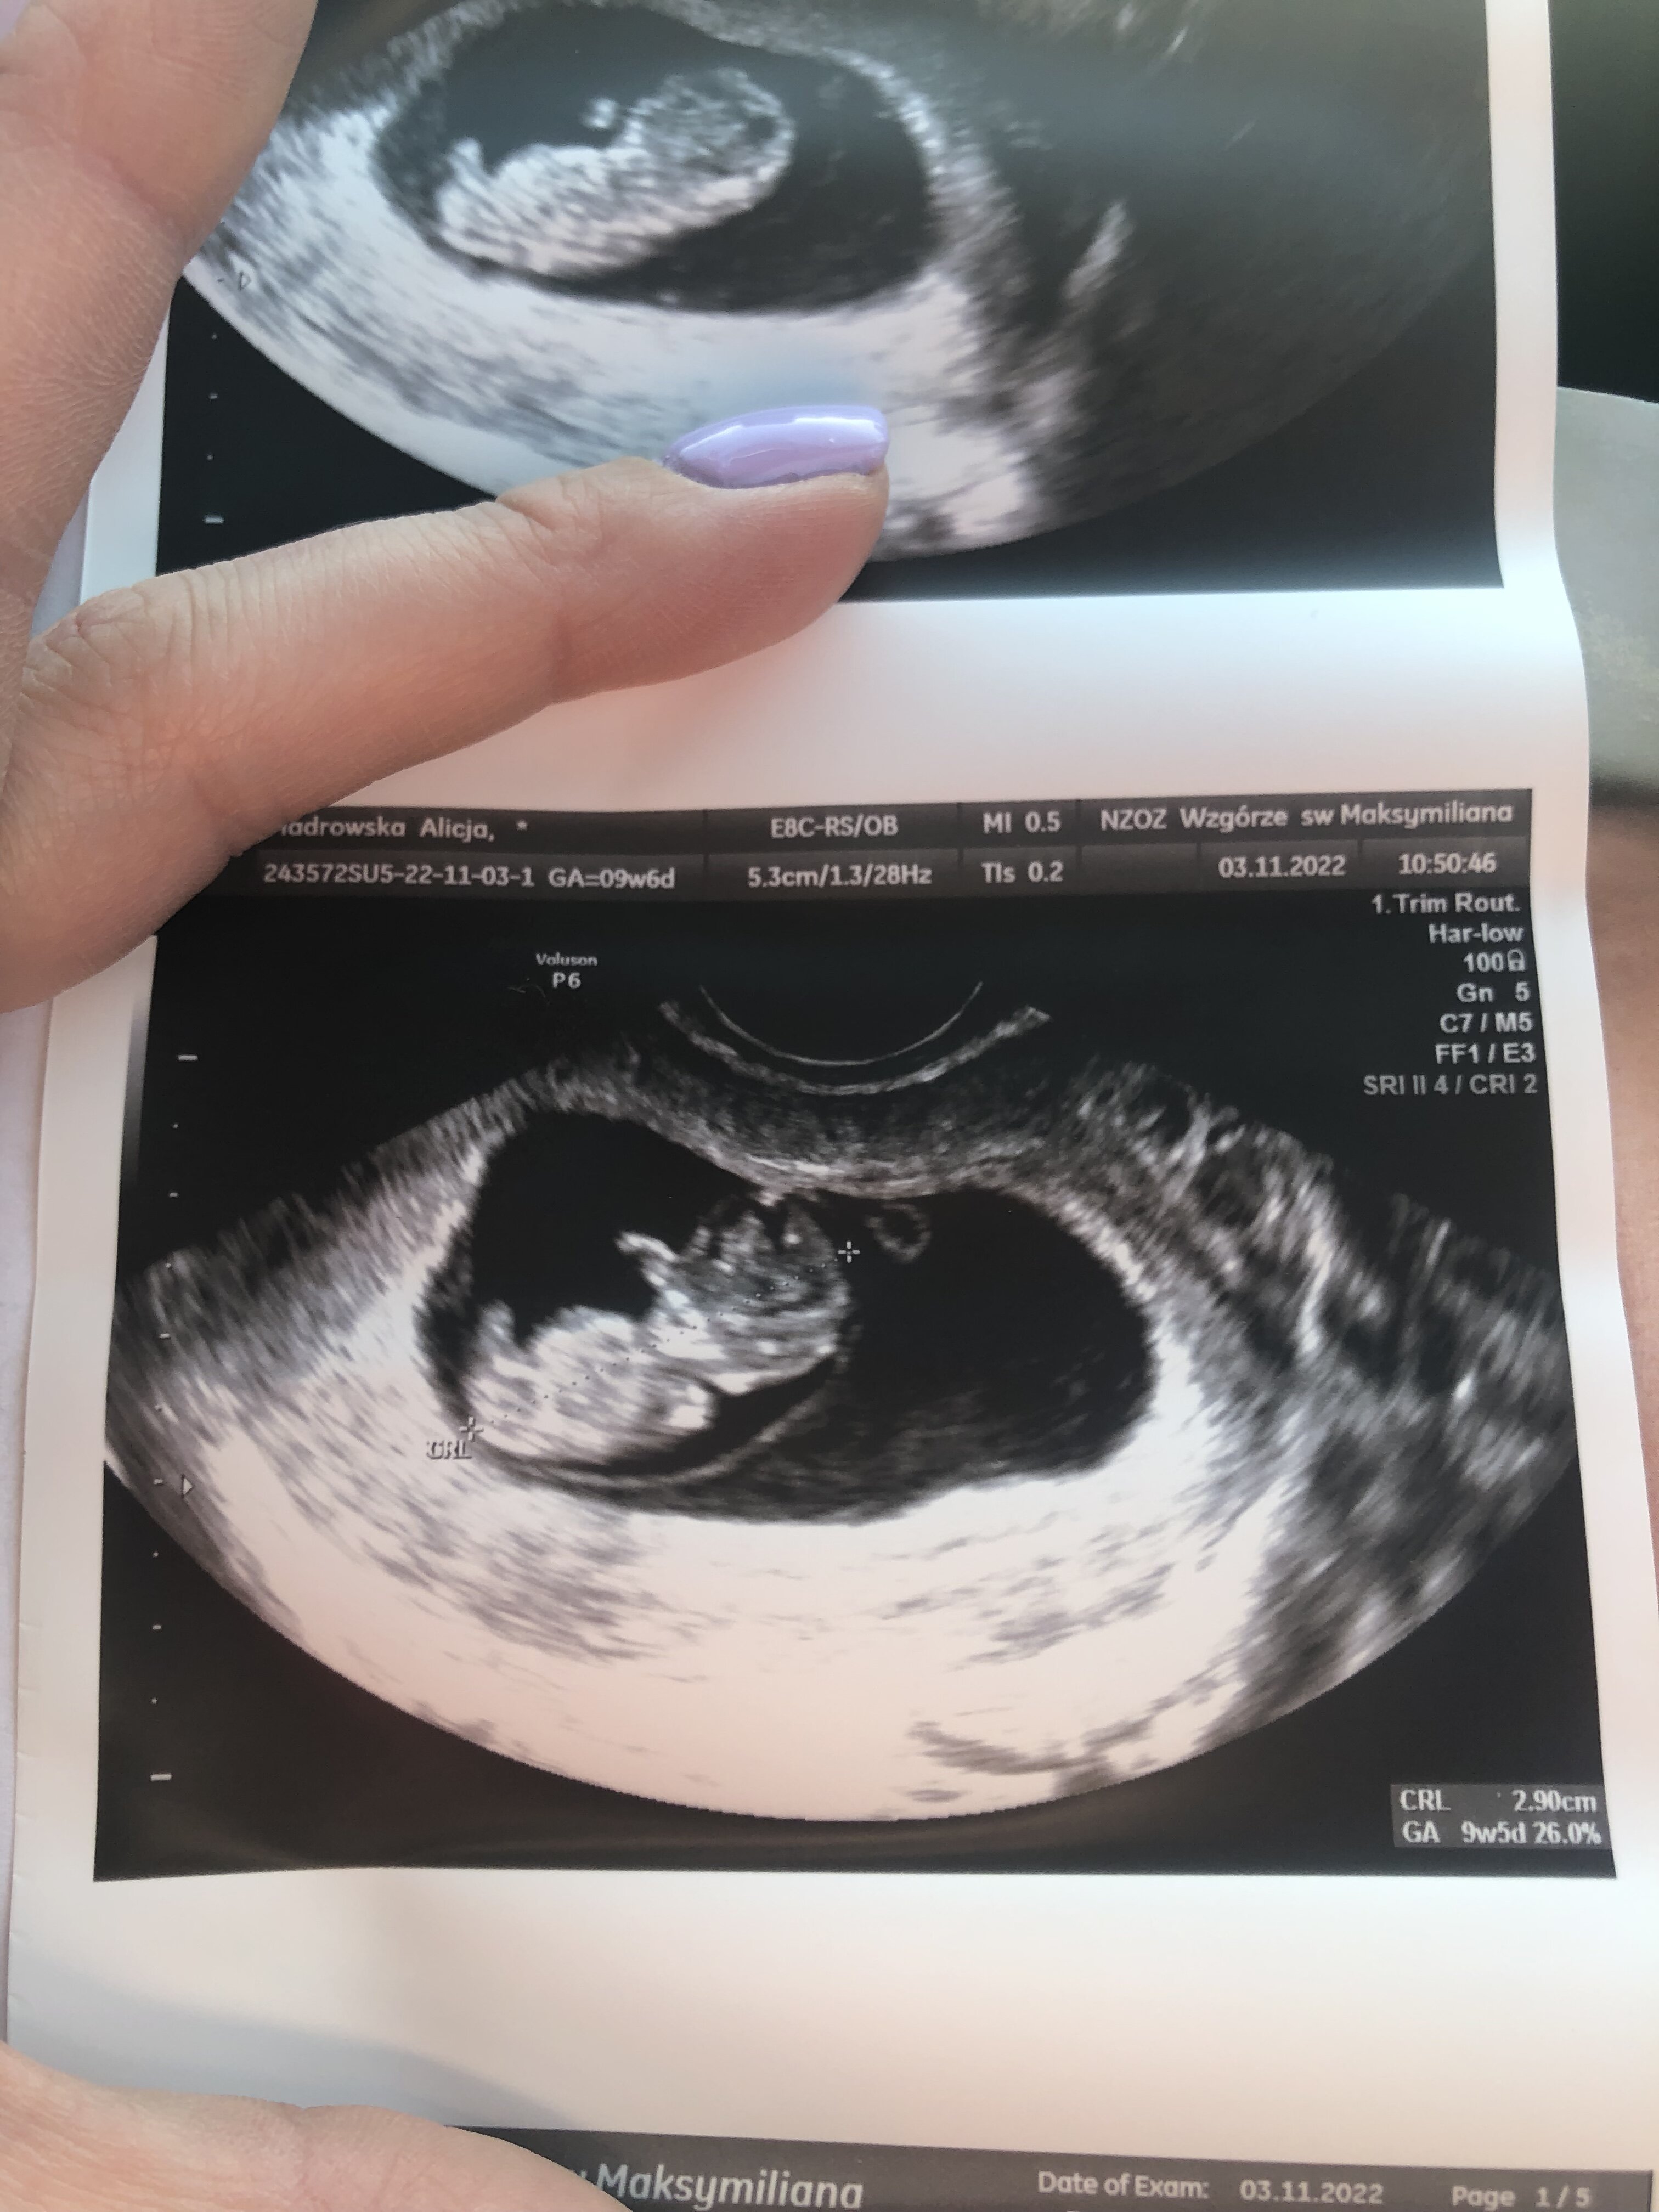

U nas 10 tydz + 0 ❤️ Wszystko dobrze tylko cukier wysoki idę jutro na krzywa cukrowa

Załączniki

• 1FECDF72-BDC6-4A69-B058-E196EB96FA8A.jpeg

1FECDF72-BDC6-4A69-B058-E196EB96FA8A.jpeg

841 KB · Wyświetleń: 131